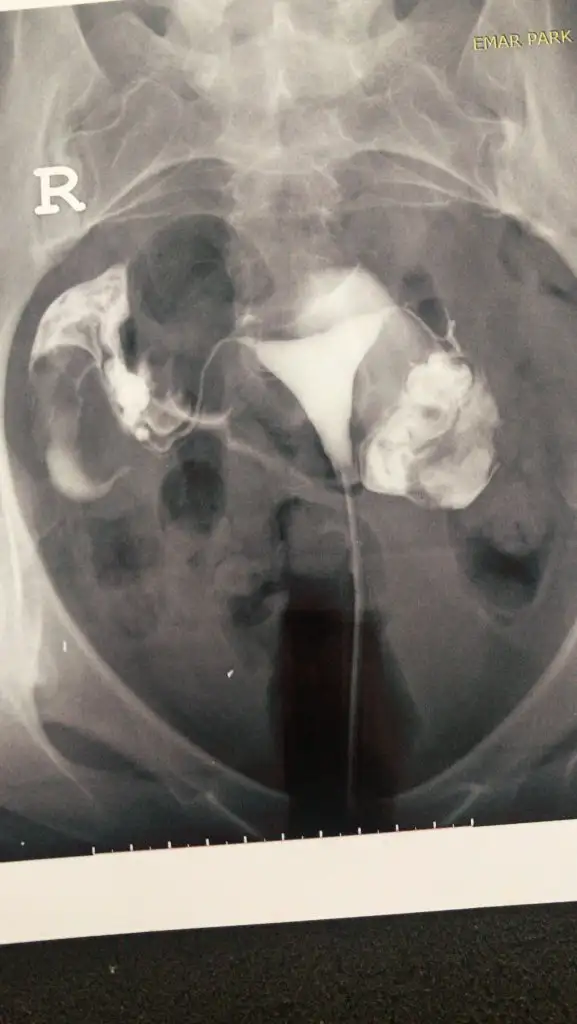

Yumurta değil bence canım. Adet sonrası hemen yumurta olmaz ki. Bu arada canın acıdı mı nasıl çektirdin hsg. Bende Cumartesi gidicem çektirmeye çok korkuyorumKızlar dün hsg çektirdim bu küçük şeyler yumurta olabilir mi

Direk yumurta değil ama yumurtalık onlar çift taraflı. O Yumurtaligin içinde yumurtalar var. Yumurtalarında azalma varsa hsg de boyutları daha küçük görünüyor. Senin gayet iyi büyük yumurtalik.Kızlar dün hsg çektirdim bu küçük şeyler yumurta olabilir mi

Her iki tubalarda açık yazıyorCanım hsgden sonra rapor kağıdı veriyorlar ya orda ne yazıyor